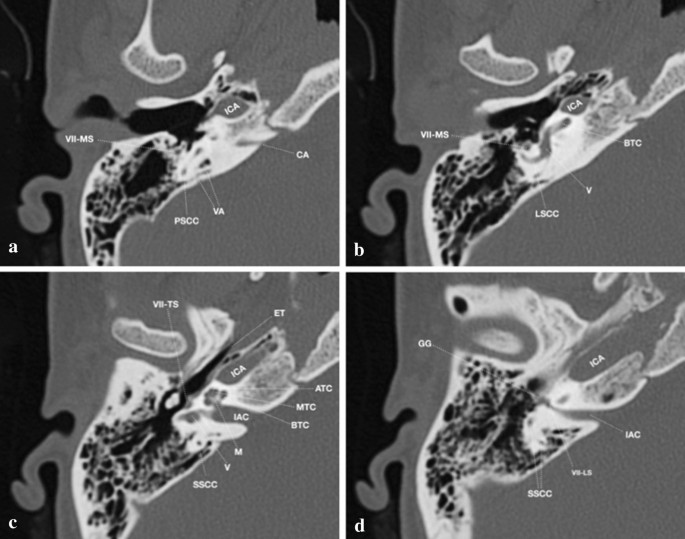

Imaging Of Inner Ear Malformations A Primer For Radiologists Springerlink

Beyond Tympanomastoidectomy A Review Of Less Common Postoperative Temporal Bone Ct Findings American Journal Of Neuroradiology